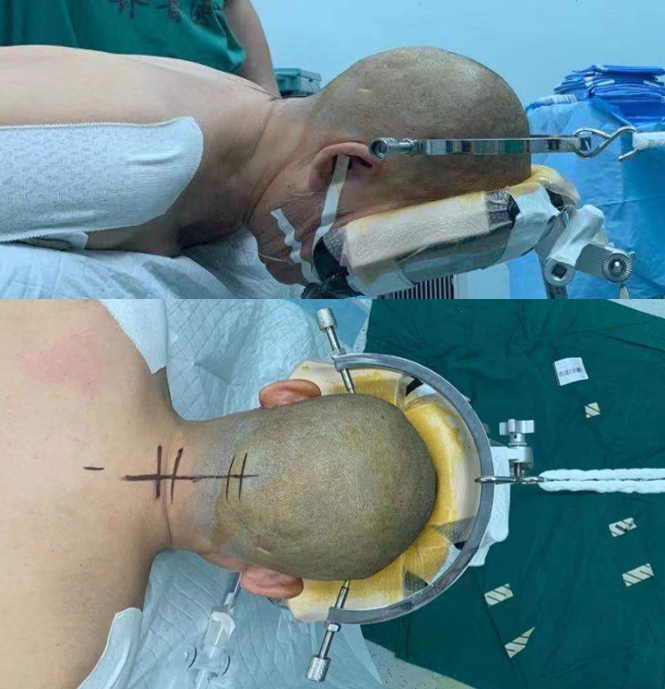

患者全麻成功后取俯卧位,头部保持中立位略后仰并牵引固定,标记枕颈部后正中长约10cm直切口,常规消毒铺巾和局麻后,依次切开皮肤、皮下组织和颈后肌肉,牵开器牵开,显露枕骨鳞部、寰枢椎至颈3的棘突和椎板,见寰枕融合,显微镜下显露双侧寰枢椎侧方关节,去除侧方关节内关节软骨并撑开,扩张侧方关节间隙,双侧侧方关节内各置入含人工骨的Cage1枚,双侧颈1-2分别置入椎弓根螺钉,取钛棒固定,然后磨钻磨除枕大孔后缘部分骨质,开窗约2*2cm,见寰枕后缘减压充分、硬膜膨隆明显,术腔彻底止血后放置引流管一根,依次关闭各层。手术经过顺利,术后患者清醒后安返病房。术后患者症状较术前明显好转。目前患者已顺利出院。

术中所见

A:手术体位、切口;B:破坏寰枢椎关节间软骨;C:寰枢椎关节间撑开并试模;D:置入Cage;E:Cage位置良好;F:置入椎弓根螺钉并钛棒固定,寰枕后缘减压充分。